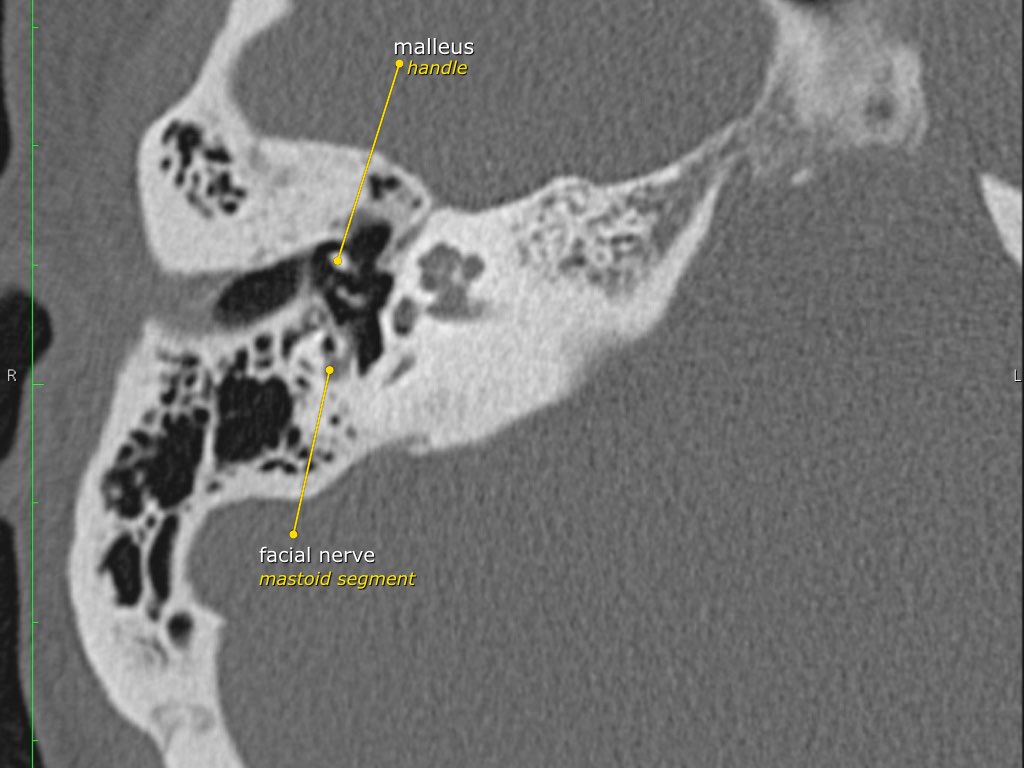

Trong bài tổng quan này, chúng tôi trình bày giải phẫu bình thường trên mặt phẳng cắt ngang (axial) và mặt phẳng cắt đứng ngang (coronal) của xương thái dương thông qua việc duyệt qua các hình ảnh.

Một số cấu trúc được thảo luận chi tiết hơn với trọng tâm là các bệnh lý liên quan.

Giải phẫu xương đá trên mặt phẳng cắt ngang (Axial)

Nhấp vào hình ảnh để phóng to.

Cuộn qua các hình ảnh.

Dây thần kinh mặt

Đoạn mê nhĩ của dây thần kinh mặt xuất phát từ ống tai trong, chạy gần như vuông góc với trục dài của xương đá, gập góc nhọn về phía trước để đến hạch gối (geniculate ganglion).

Tại hạch gối, dây thần kinh mặt tạo thành một khúc quặt hình chữ U (genu thứ nhất của dây thần kinh mặt) để chạy ra phía sau theo đoạn nhĩ dọc theo thành trong của thượng nhĩ.